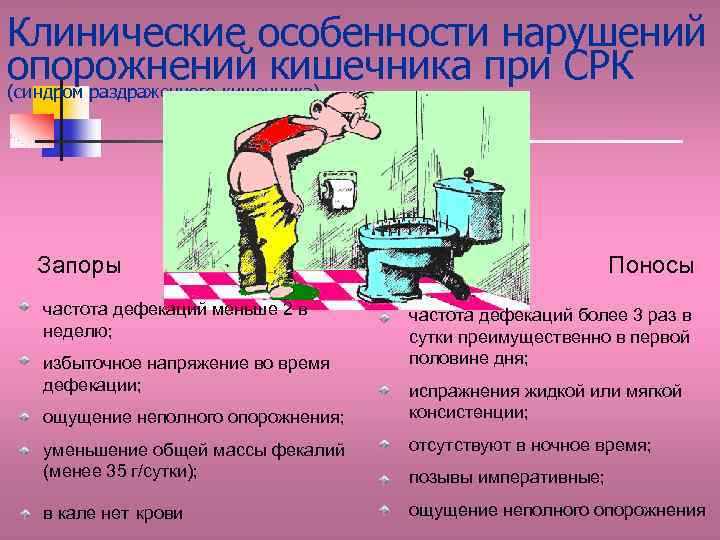

Клинические особенности нарушений опорожнений кишечника при СРК (синдром раздраженного кишечника) Запоры частота дефекаций меньше 2 в неделю; избыточное напряжение во время дефекации; ощущение неполного опорожнения; Поносы частота дефекаций более 3 раз в сутки преимущественно в первой половине дня; испражнения жидкой или мягкой консистенции; уменьшение общей массы фекалий (менее 35 г/сутки); отсутствуют в ночное время; в кале нет крови ощущение неполного опорожнения позывы императивные;

Клинические особенности нарушений опорожнений кишечника при СРК (синдром раздраженного кишечника) Запоры частота дефекаций меньше 2 в неделю; избыточное напряжение во время дефекации; ощущение неполного опорожнения; Поносы частота дефекаций более 3 раз в сутки преимущественно в первой половине дня; испражнения жидкой или мягкой консистенции; уменьшение общей массы фекалий (менее 35 г/сутки); отсутствуют в ночное время; в кале нет крови ощущение неполного опорожнения позывы императивные;